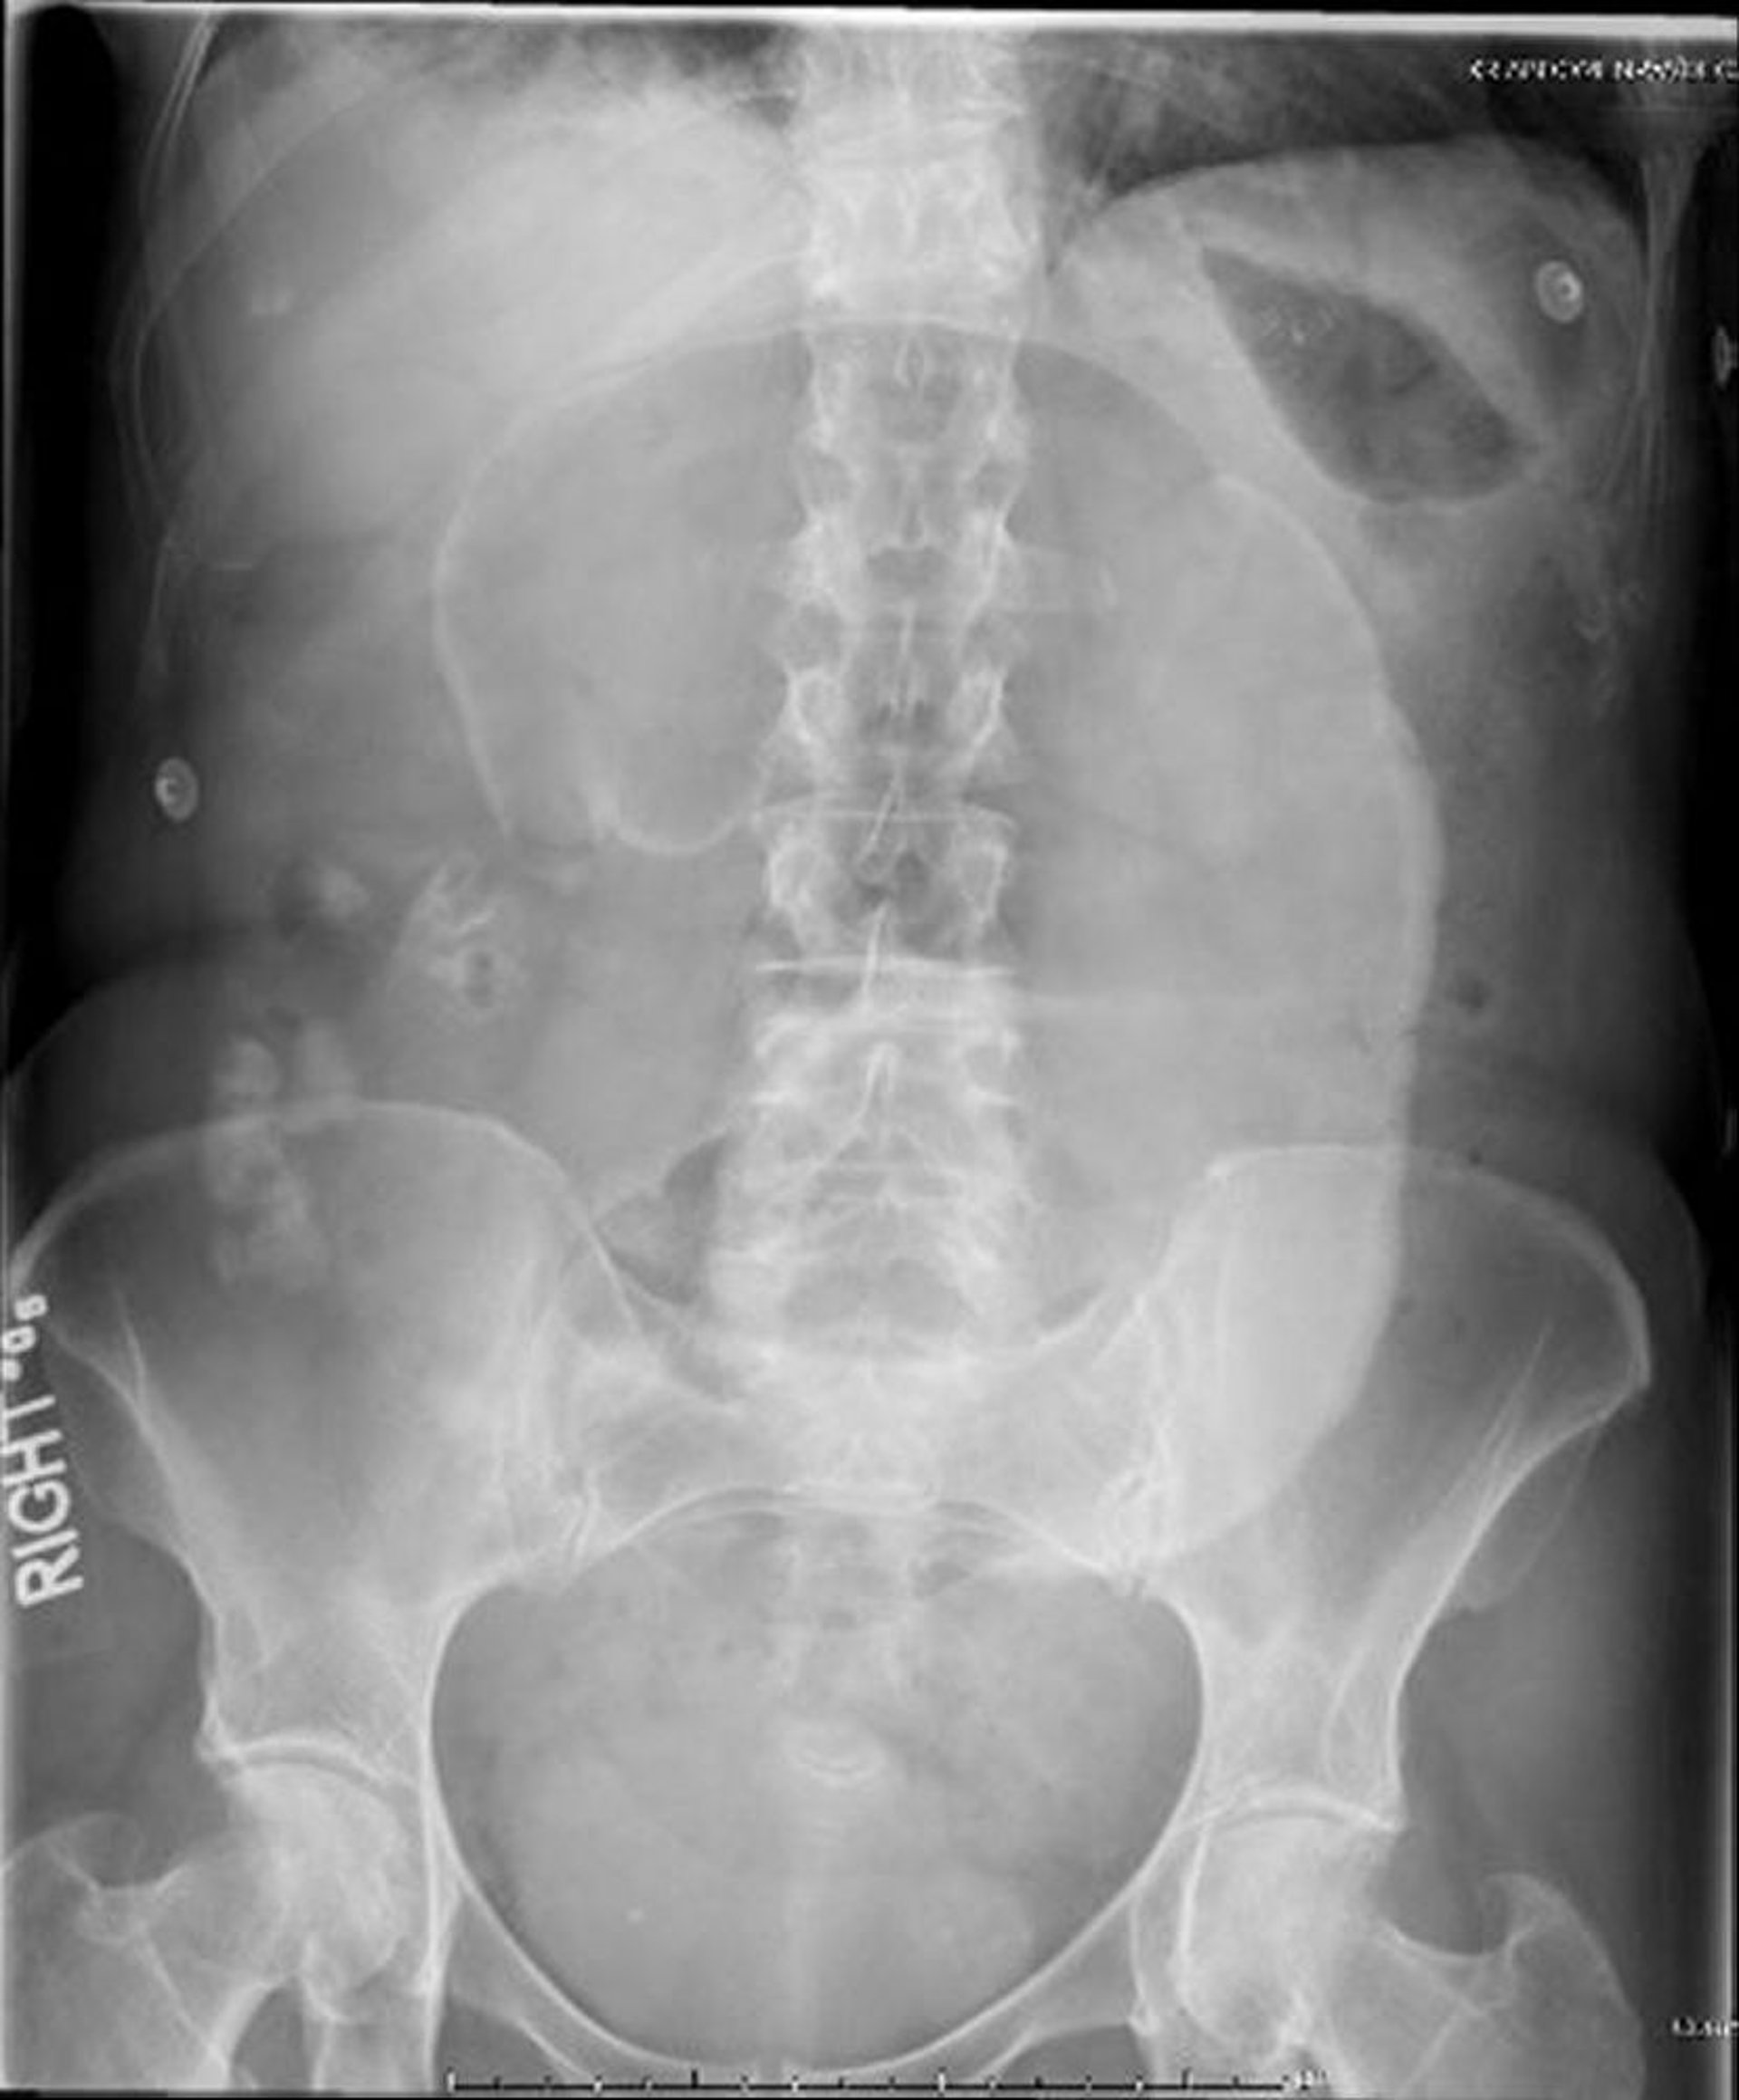

Xoắn manh tràng (phim chụp X-quang bụng)

Trong phim chụp X-quang bụng này, manh tràng bị xoắn quanh mạc treo, khiến cho dấu hiệu "hạt cà phê" giãn ra nhô về phía góc phần tư trên bên trái.

Hình ảnh do bác sĩ Parswa Ansari cung cấp